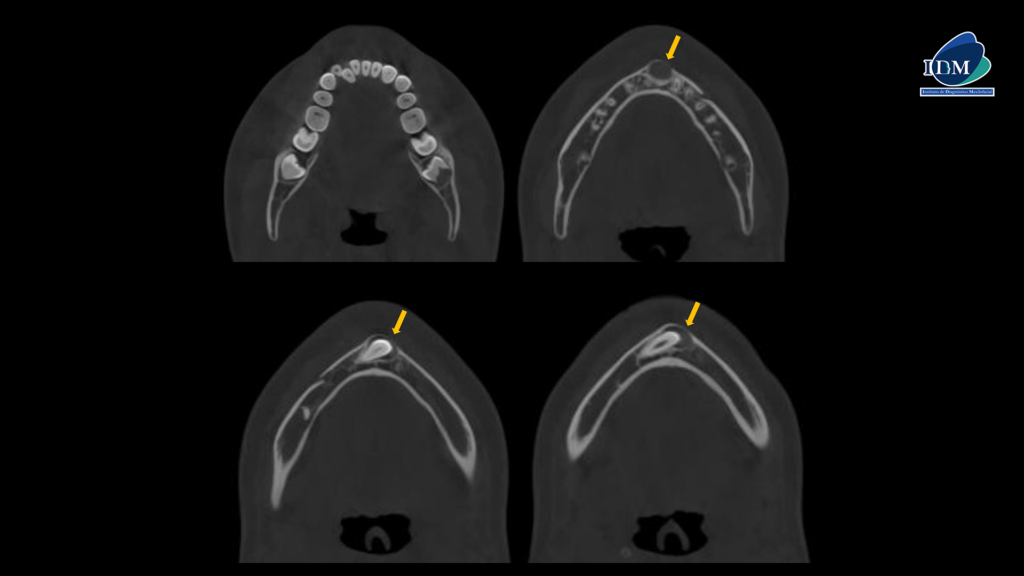

A la evaluación de la tomografía volumétrica (cone beam) en los cortes axiales (Figura 2) y transaxiales (Figura 3), se observa pieza 43 retenida, mesioangulada, localizada en sínfisis mandibular, orientada hacia la tabla ósea vestibular y con presencia de imagen isodensa pericoronaria de forma ovalada de limites definidos insertada a nivel de la unión amelocementaria, de dimensión de 9.9 x 12.15 x 13.5 mm que se extiende de mesial de 33 a distal de 42 ocasionando una leve expansión y adelgazamiento de la tabla ósea vestibular. A demás de presentar en la pieza 48 la presencia de imagen hipodensa ovalada localizada por debajo del limite amelodentinario y ubicación central.

CORTES AXIALES

CORTES TRANSAXIALES